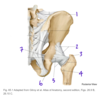

Fig. 56.2 Adapted from Gilroy et al. Atlas of Anatomy, 2nd edition, Figs. 26.4 A, 26.4 B

Which structure is labeled by #12?

Semitendinosus

Which muscle is labeled by #4?

Piriformis

Which structure is indicated by #2?

What is its primary function?

Piriformis

Lateral rotation of the hip